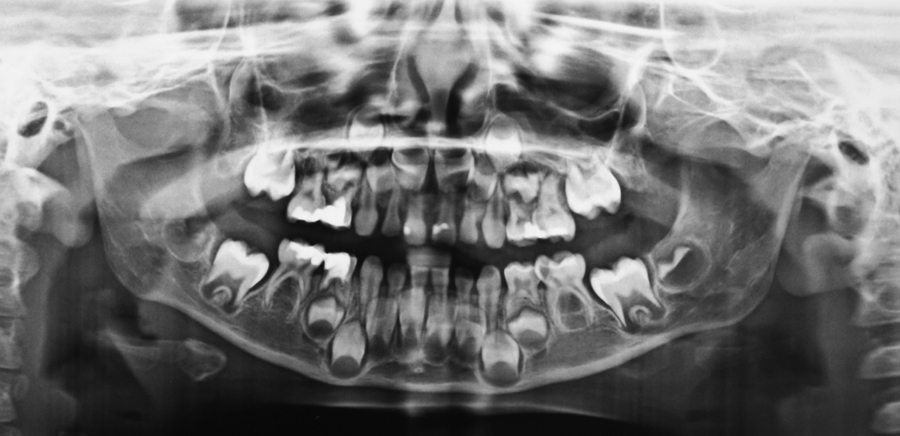

Figure 1. Panoramic image of the patient at the time of consultation

INTRODUCTION There is a growing trend towards performing community-based dental treatment under deep sedation or general anaesthesia. Indications for dental treatment under anaesthesia may include patients with extensive treatment needs, acute situational anxiety, uncooperative age appropriate behaviour, immature cognitive function, disabilities or medical conditions.1 Patients known or suspected to be susceptible to malignant hyperthermia (MH) … Read more